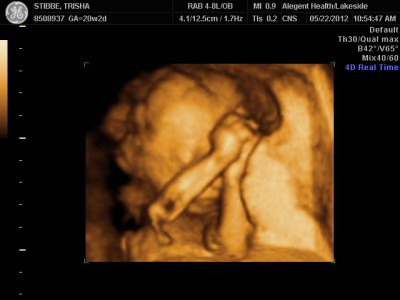

Ultrasound Day!